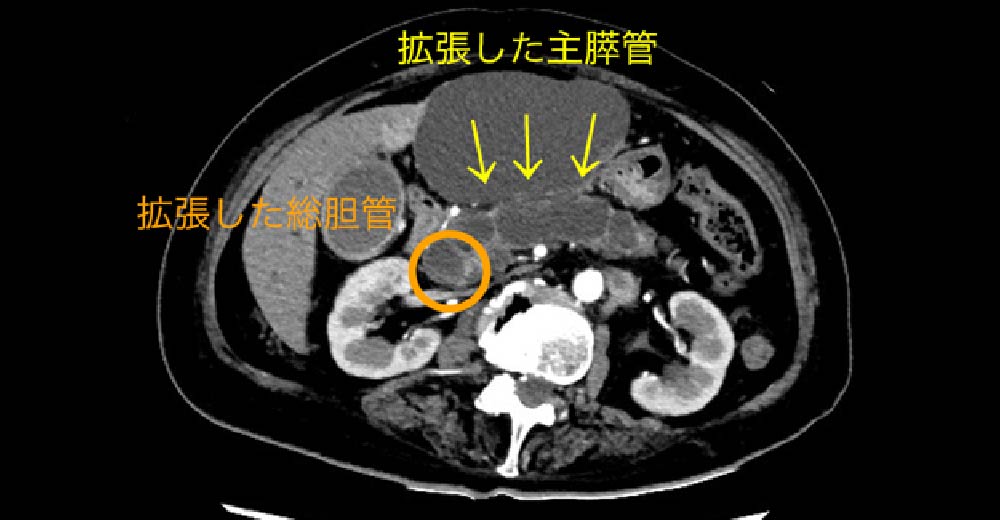

PV:門脈 SMA:上腸間膜動脈 SpV:脾静脈

2型糖尿病で、当院に転医された患者さんです。紹介元で1度も腹部エコーをされたことがなかったのですが、糖尿病の基本管理とおり定期腹部エコーにて、診断された“通常型膵がん”の症例です。背景疾患に、“糖尿病”がある場合は、常に新規“膵がん”発生を念頭において、外来観察する必要があります。

この症例では“膵がん”腫瘤が、生存に重要な“門脈”と“上腸管膜動脈”に近接しており、根治切除できるかどうかぎりぎりの患者さんです。切除できなければ、近代の医学においても予後は極めて不良です。

膵がん 膵がん

糖尿病診断契機に診断された、“膵がん”の1例です。

膵臓は臓器特性上、周囲に“生存に必須な血管が存在しており、進行した状態では、まず救命できません。糖尿病罹患患者さんでは、”膵がん“のリスクが高く、常に監視することが必要です。